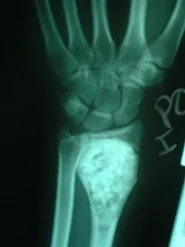

Paciente del sexo femenino de 15 años de edad, portadora de Quiste Óseo Aneurismático de radio derecho, quien había sido intervenida hace aproximadamente 1 año en otro centro, donde le practicaron curetaje de la lesión y relleno del quiste con injerto de cresta ilíaca. La lesión recidiva, acude por la consulta del Dr. Alberto A. Martínez Conde, donde previa revisión de las laminas histológicas por parte del Dr. David Mota, se practicó curetaje amplio del quiste y relleno de la cavidad con Hidroxiapatita sintética e injerto de cresta ilíaca, se estabilizo el radio con tutor externo.

El resultado post-operatorio con seguimiento de 1 año fue excelente, sin signos de recidiva